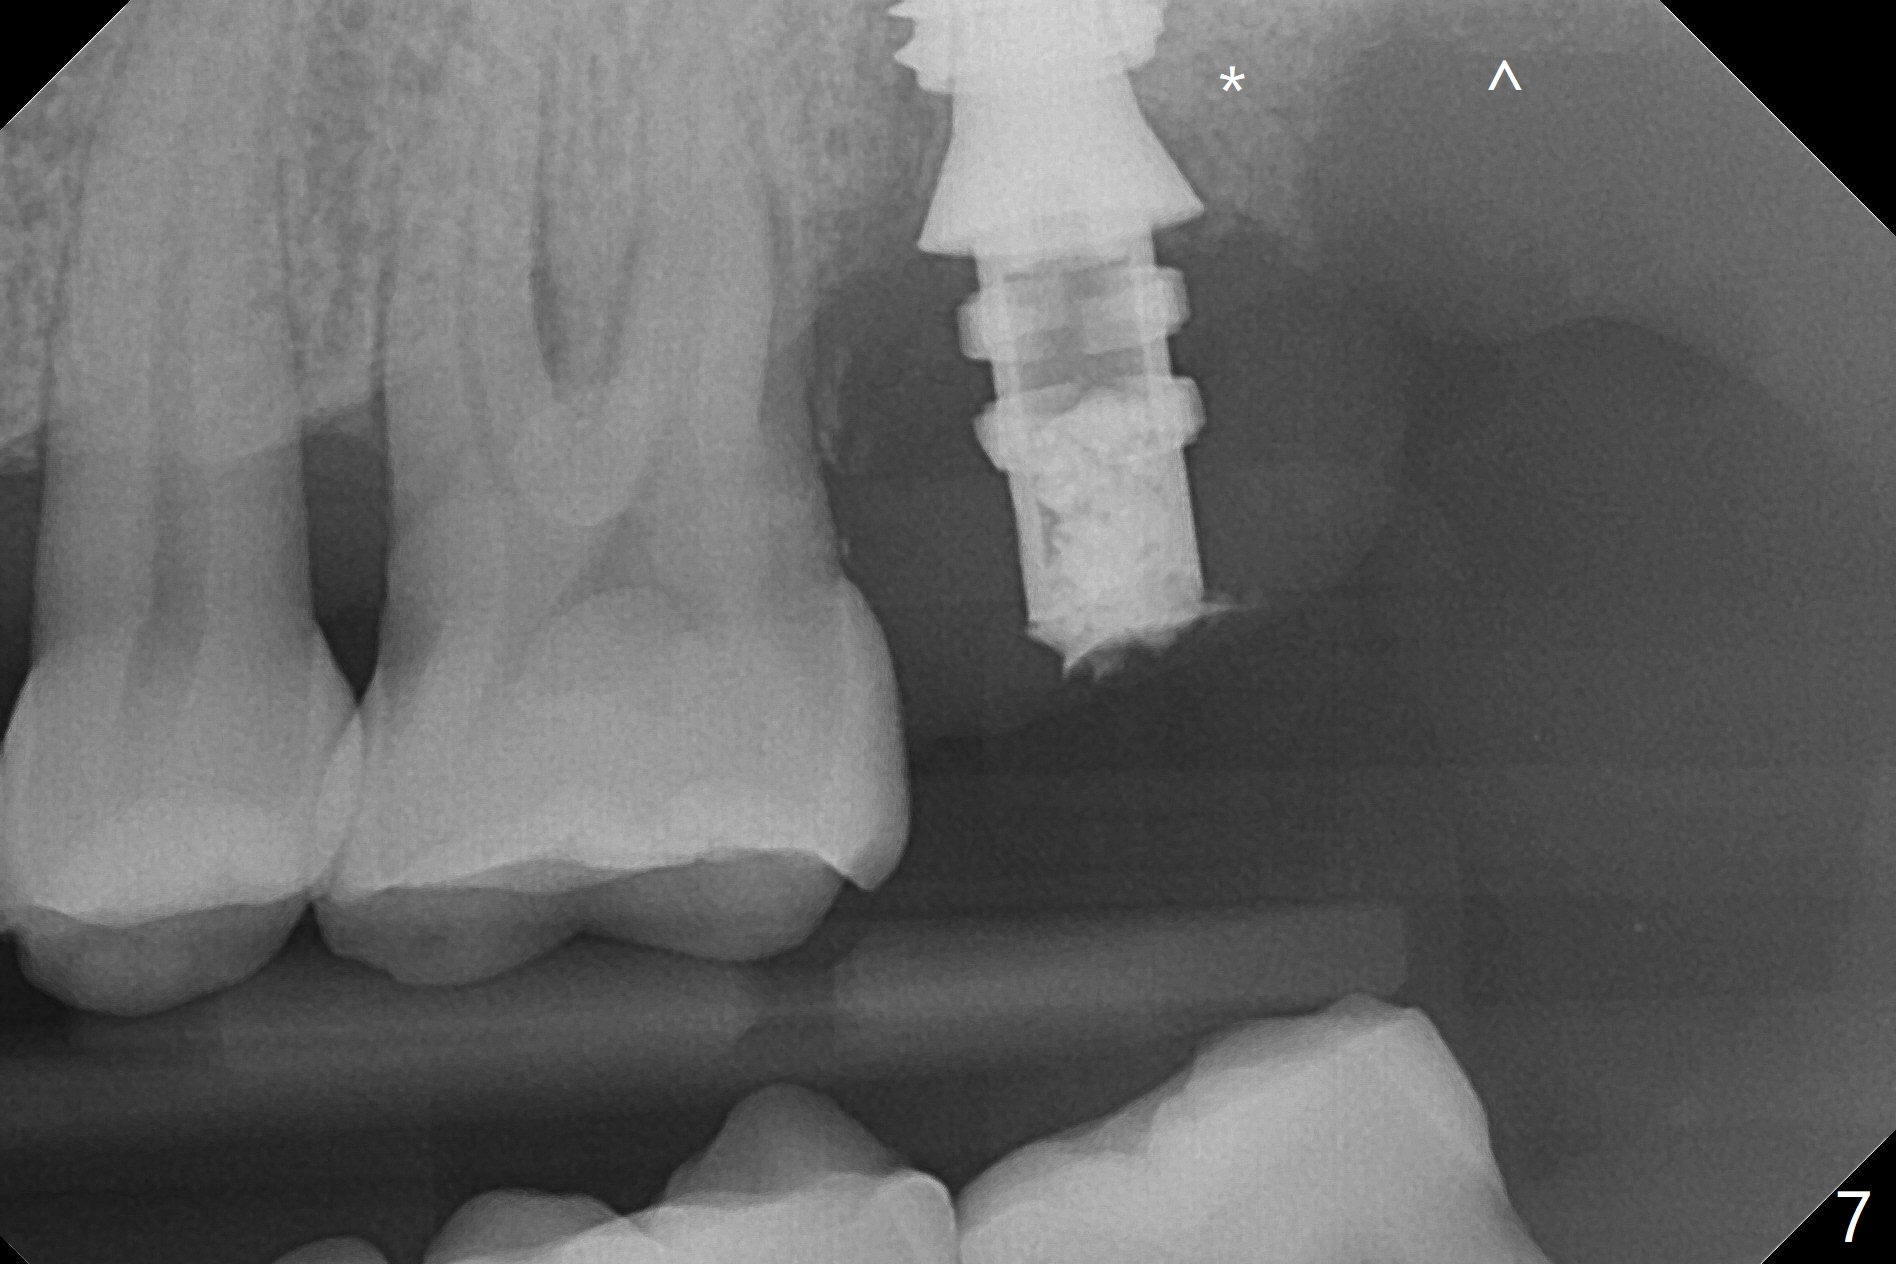

Although the buccal (Fig.1 (mesial view of the extracted tooth #15): B) root is larger than the palatal (P) one, the palatal socket is larger than the buccal one (Fig.2 white area) because of the bone loss of the former. For better restoration, osteotomy (Fig.2 red line) is initiated in the buccal slope of the septum (S) so that the final osteotomy is in the middle of the whole socket (Fig.3 red box). In fact a 3 mm stopper is not used because of the slope and the clumsy stopper. Stopper would be indicated if the bottom of the bone were flat. At first a 4x10 mm dummy implant is placed with stability (Fig.4). After further osteotomy and sinus lift (Fig.6 red dashed line: sinus floor), a 5x10 mm implant is placed with 30 Ncm, followed by insertion of a 5.2x8(2) mm temporary abutment (Fig.5,6). The latter holds an immediate provisional and Vanilla Graft/Osteogen (Fig.7 *) in place (^: distal crestal bone). Although the bone looks normal around the implant 7.5 months postop (Fig.4), the implant is unstable, probably due to the large preexisting defect. In contrast the implant placed at the healed site of #3 is stable 6.5 months postop. The 8x5 mm healing abutment that dislodged for 1 day could not return. A 6x5 mm one is used; it appears that the bone density mesial and distal to the implant is low (Fig.9 *). The implant looks normal and is stable 13 months postop (Fig.10). A 5.7x5.5(5) mm cementation abutment is placed for a provisional (progressive loading, Fig.11). There is no pain associated with the provisional for mastication. Impression is taken 7 days later. The patient has pain when the permanent crown is cemented. It appears that the implant does not osteointegrate and should be removed. A 6x14 mm tissue-level implant will be immediately placed following a 5 and 6x14 mm taps and bone graft and PRF (Metronidazole). In fact there is no pain when the existing abutment is torqued at 35 Ncm 1 year 8 months postop (Fig.12). The mesiogingival portion of final restoration (Fig.13 arrowheads) should be bulky so that the gingival embrasure (red dashed line) is minimal to reduce food impaction.